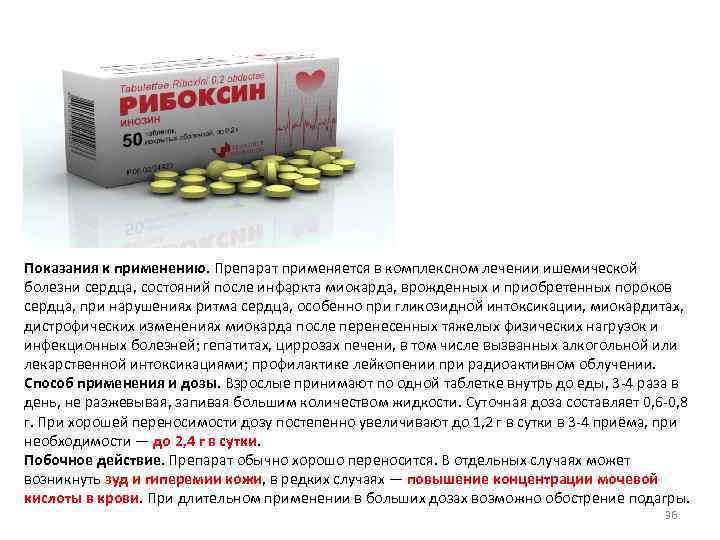

Показания к применению. Препарат применяется в комплексном лечении ишемической болезни сердца, состояний после инфаркта миокарда, врожденных и приобретенных пороков сердца, при нарушениях ритма сердца, особенно при гликозидной интоксикации, миокардитах, дистрофических изменениях миокарда после перенесенных тяжелых физических нагрузок и инфекционных болезней; гепатитах, циррозах печени, в том числе вызванных алкогольной или лекарственной интоксикациями; профилактике лейкопении при радиоактивном облучении. Способ применения и дозы. Взрослые принимают по одной таблетке внутрь до еды, 3 -4 раза в день, не разжевывая, запивая большим количеством жидкости. Суточная доза составляет 0, 6 -0, 8 г. При хорошей переносимости дозу постепенно увеличивают до 1, 2 г в сутки в 3 -4 приёма, при необходимости — до 2, 4 г в сутки. Побочное действие. Препарат обычно хорошо переносится. В отдельных случаях может возникнуть зуд и гиперемии кожи, в редких случаях — повышение концентрации мочевой кислоты в крови. При длительном применении в больших дозах возможно обострение подагры. 36